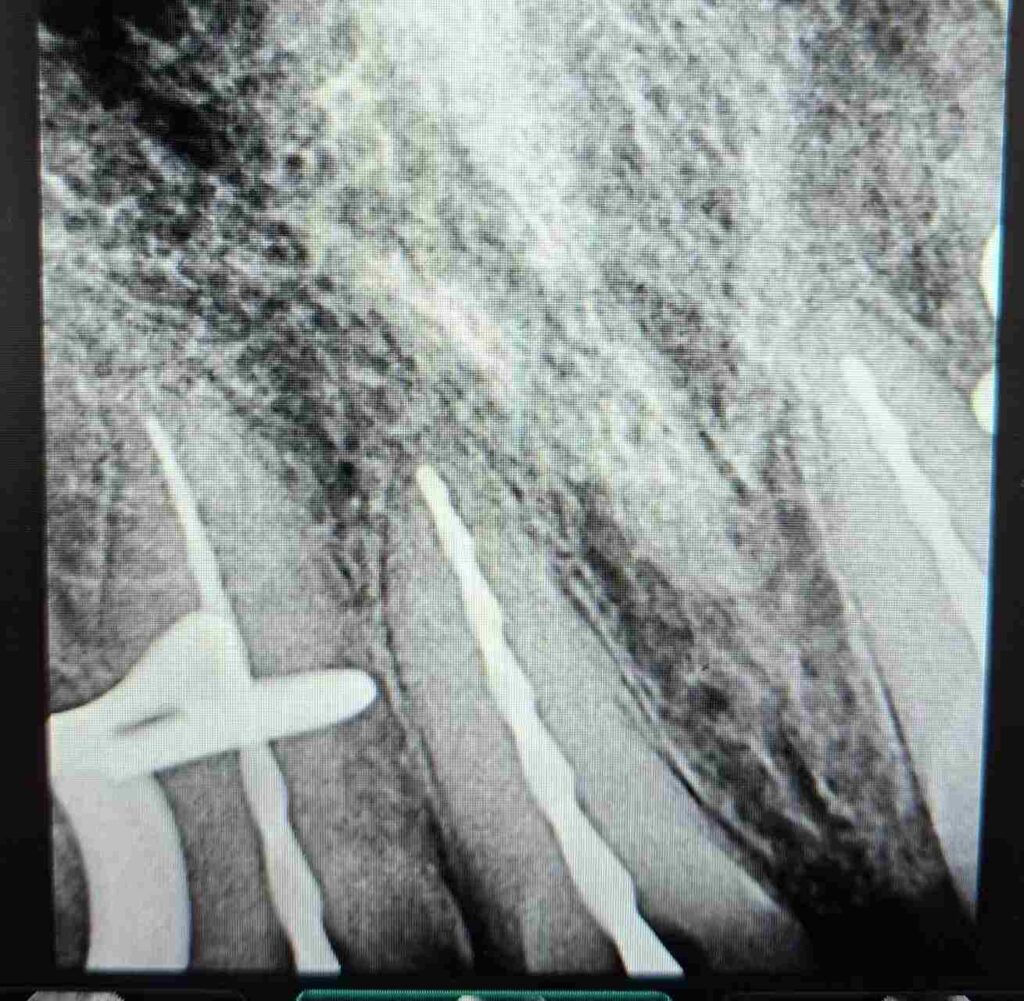

El procedimiento se realizó bajo aislamiento absoluto. Se procedió a la localización y permeabilización de los conductos radiculares. La preparación biomecánica se llevó a cabo con el sistema reciprocante Recip One File Blue de Rogin Dental, que permitió una instrumentación eficiente, controlada y segura, optimizando la limpieza y conformación del sistema de conductos.

Durante todo el protocolo se realizaron irrigaciones activas con soluciones desinfectantes, garantizando la eliminación completa de detritos y microorganismos. Finalmente, se completó la obturación tridimensional del sistema radicular, logrando un sellado hermético confirmado por control radiográfico.